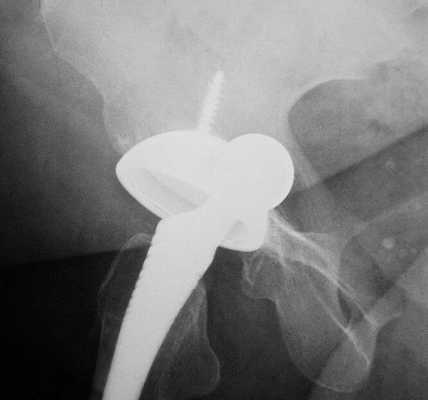

Смещение протеза

В результате данного явления вживленный имплантат не только теряет фиксацию и расшатывается, но и приводит к постепенному или резкому изменению длины ног. В таком случае требуется немедленная консультация у врача и повторная операция на конечности. К основным причинам можно отнести следующие:

- неправильная установка имплантата;

- недостаточный контакт между поверхностями сустава и протеза;

- сильные нагрузки на имплантат;

- непрочное соединение компонентов изделия.